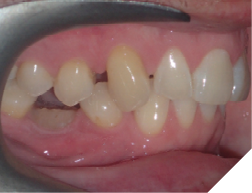

5. Oral hygiene (Fig. 12AB)

Checking for:

i. Bleeding upon probing

ii. Plaque/calculus amount at the gingival of the fixed retainer

iii. Any gingival recession or hyperplastic gingival tissues

Fig. 12A

Fig. 12B